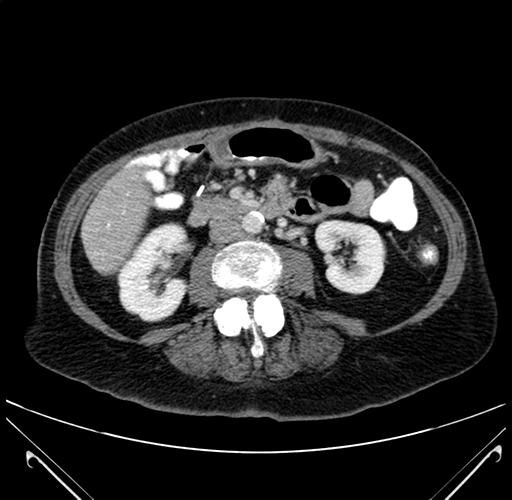

Pre-Chemo: Axial Venous